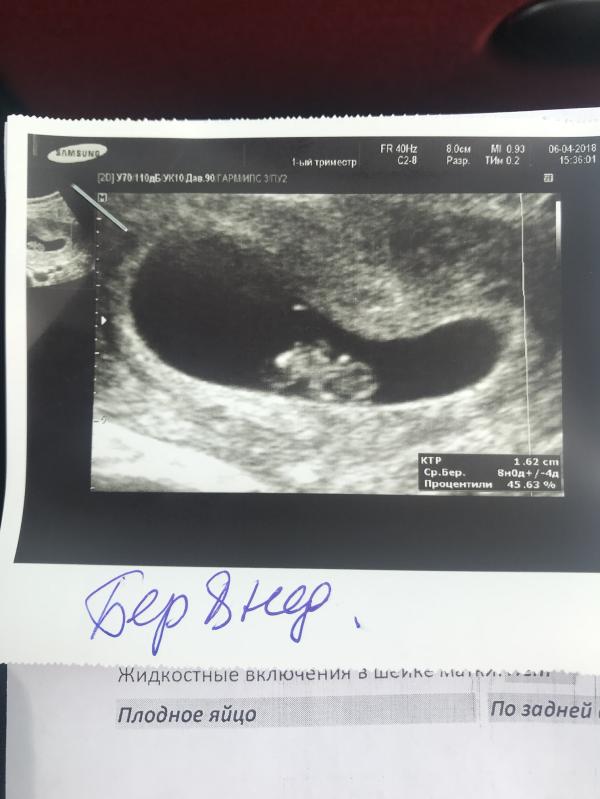

Сходила на УЗИ, все хорошо. Сердцебиение есть, угрозы нет. Растёт во мне ещё один Скорпион 😁

@preggy_user, я сейчас в другом городе у родителей, здесь прошла. Делали через живот на полный мочевой пузырь. Да, для себя, чтобы убедиться что в матке и сердцебиение есть.